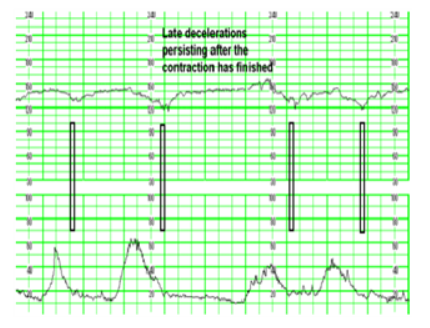

⓶ 후기 감퇴(만기하강) – latedeceleration

FHR이 수축 극기에서 떨어지기 시작해 자궁 수축이 멈춘 뒤에도 회복이 지연된다.

원인 : 자궁과 태반순환이 부적절 자궁-태반혈류 방해(자궁수축) >> 제대정맥혈류 감소 >> 태반내 산소공급 저하)

(1) 산모의 저산소증(만성빈혈)(2) 저혈압/고혈압(3) 자궁의 고조장상태(4) 태반혈류부족(5) 태반박리

간호 중재 (1) 좌측 상 (2) 정맥 주입 속도를 늘린다.(3)자궁수축시 중단(Oxytocin 중단)(4) O25-10L 공급(mask)(5) 양수 내 태변 착색 관찰(태아 저산소혈증시 양수 내에서 태변 가능성 증가) (6) 후기 하강 지속시 분만 종결(C/SEC 분만)